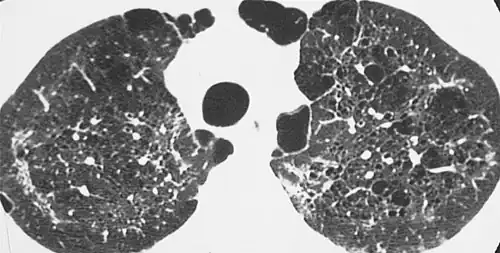

X-ray and CT of ground glass opacities and pneumothorax in pneumocystis pneumonia.[7]

The diagnosis can be confirmed by the characteristic appearance of the chest X-ray and an arterial oxygen level (PaO2) that is strikingly lower than would be expected from symptoms. Gallium 67 scans are also useful in the diagnosis. They are abnormal in about 90% of cases and are often positive before the chest X-ray becomes abnormal. Chest X-ray typically shows widespread pulmonary infiltrates. CT scan may show pulmonary cysts (not to be confused with the cyst-forms of the pathogen).